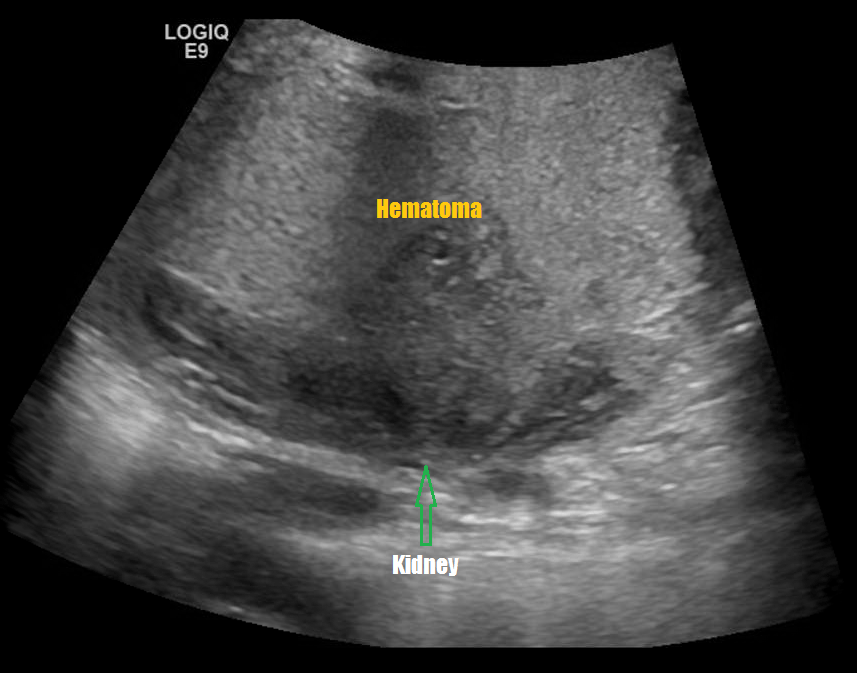

Renal Trauma

Renal trauma accounts for approximately 1-5% of all trauma admissions and as many as 10% of patients who sustain abdominal trauma. Injuries can range from contusions to life threatening injury. The types of trauma include penetrating (gsw, knife), blunt force (mva, sports injury), post procedure etc..

Patients may have abdominal/flank pain on the affected side, hematuria may also be present.